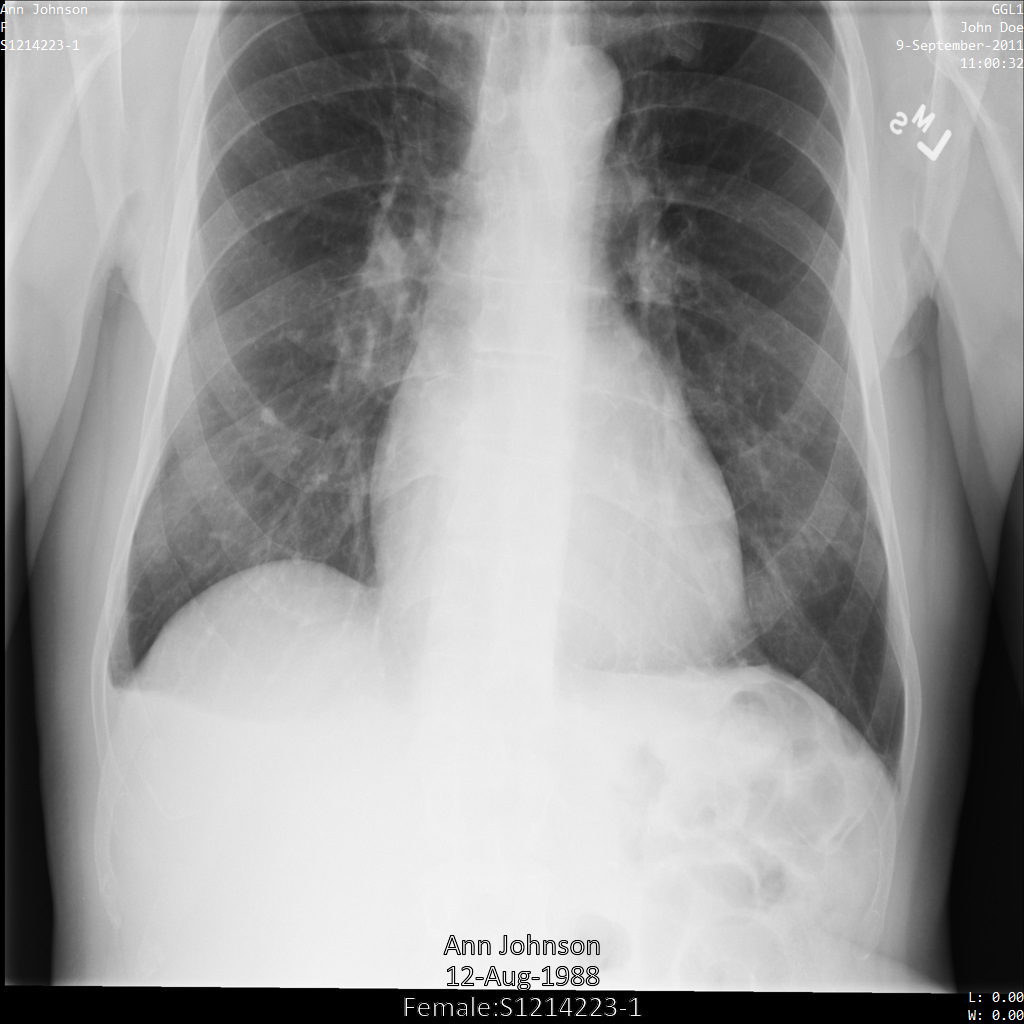

Dopo aver inviato l'immagine all'API Cloud Healthcare utilizzando il

profilo di filtro dei tag ATTRIBUTE_CONFIDENTIALITY_BASIC_PROFILE, l'immagine viene visualizzata

come segue. Sebbene i metadati visualizzati negli angoli superiori dell'immagine

siano stati oscurati, le informazioni sanitarie personali incorporate nella parte inferiore dell'immagine rimangono.

Per rimuovere anche il testo integrato, consulta

Oscuramento del testo integrato nelle immagini.